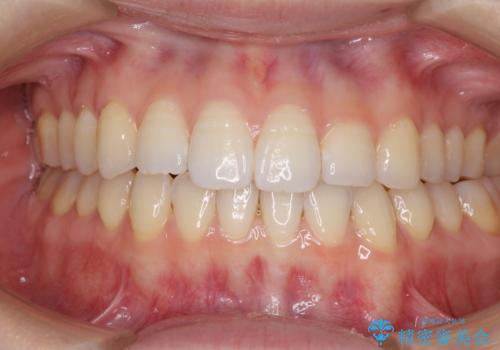

オープンバイトのインビザラインを用いた再矯正

- 矯正治療の後戻りを気にして来院された患者様です。

オープンバイト(前歯の開咬)と下顎骨の偏位による不正咬合が認められました。

骨格の偏位による不正咬合は改善しきれないことを理解いただいた上で、インビザラインにて矯正治療を行うこととしました。

オープンバイトは後戻りを起こしやすいため、極力そのリスクを軽減するため、奥歯を圧下させるように治療を進めていきました。

下顎骨の偏位が顕著であったため、上下の正中を合わせることはできませんでしたが、患者様には大変満足していただきました。